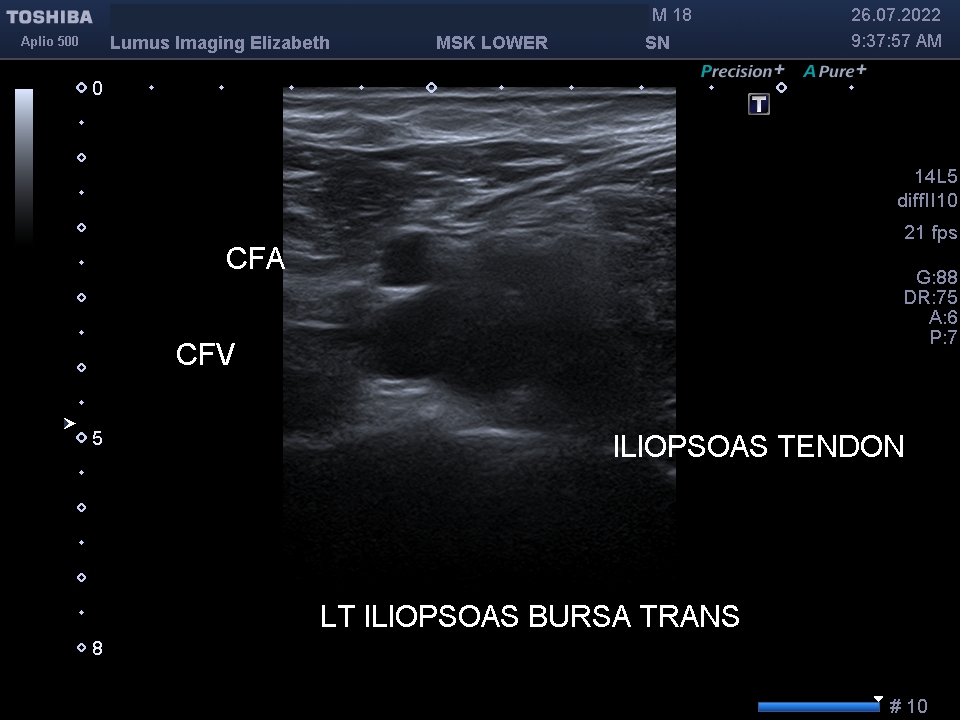

I202207261120140320015

Son Nguyen

26/07/2022